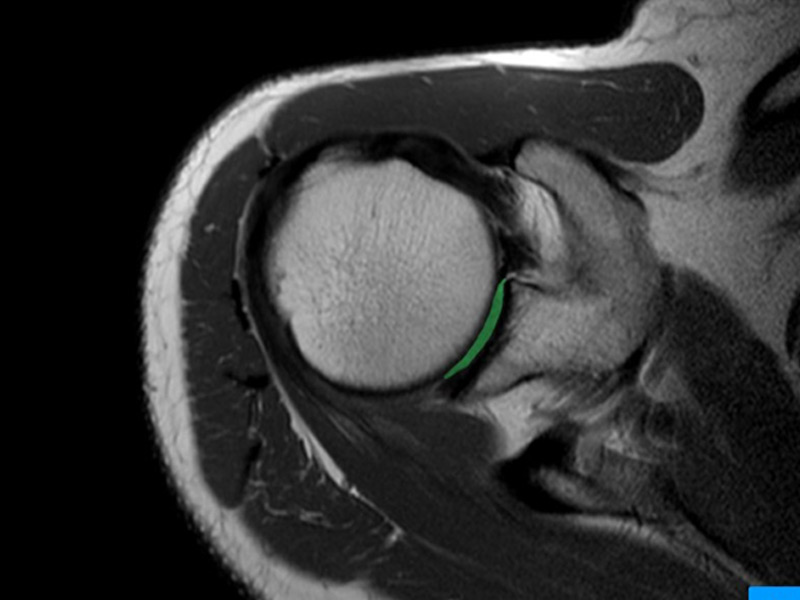

Resonancia magnética de hombro

Se utiliza para diagnosticar diversas dolencias de tejidos blandos, tendones, ligamentos, bursas, músculos y la articulación glenohumeral y evaluar lesiones del manguito rotador.

• Artroresonancia:

Hombro, muñeca, cadera, entre otras

La artroresonancia es un estudio que tiene como objetivo evaluar el estado de estructuras ubicadas dentro o rodeando a una articulación. Para ello se debe distender esa articulación mediante la inyección de un líquido compuesto mayormente por agua estéril (solución fisiológica) y una pequeña cantidad de contraste. La inyección se realiza con anestesia local en la piel y se controla con Tomografía Computada que la aguja alcance el punto deseado para distender la articulación. Es un procedimiento que se tolera sin dificultades y que no altera la vida habitual del paciente, que puede reintegrarse sin dificultad a sus tareas cotidianas.